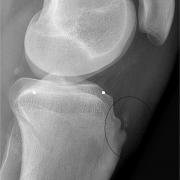

If you look at the X-ray now - at the area circled in black - you will be able to appreciate that there is some distortion of the main bone in the tubercle region, and you will also see the completely separate 'ossicle'. We know that the person has reached skeletal maturity because there is no longer any growth plate visible on the two long bones - these have already fused and become bone.